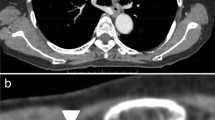

All 40 facial arteries from 20 patients were successfully imaged using 3D PC-MRA and CE-MRA. Of these, 15 arteries (37.5%) imaged using 3D PC-MRA (Fig. 2a) and 21 (52.5%) using CE-MRA (Fig. 2b) were exactly delineated by both radiologists. Because the enhancement of facial arteries is associated with contrast media (CM)-induced T1-shortening of the blood, it may be sometimes difficult to differentiate the small arteries from neighboring tissues due to CM contamination with CE-MRA compared with 3D PC-MRA (Fig. 3). For 1 of the 20 patients, the signals of facial arteries were lost with 3D PC-MRA but not with CE-MRA (Fig. 4).

With a proper setting of acquisition timing following the administration of intravenous CM injection, CE-MRA is considered a promising method for the visualization of facial arteries [2, 8,9,10,11]. However, two factors should be considered when applying CE-MRA: complication of the delineation of facial arteries due to CM contamination of neighboring tissues (Fig. 3b) and potential risk of nephrogenic systemic fibrosis following the administration of gadolinium-based CM in patients with renal insufficiency [27, 29, 30]. Non-CE-MRA is a viable alternative method for the visualization of the main arteries in the neck region. 3D PC-MRA based on blood flow velocity has minimal background tissue intensity and demonstrates comparable results to CE-MRA in terms of the visualization of facial arteries (Figs. 2 and 3). In this study, there was no significant difference between CE-MRA and 3D PC-MRA in terms of the diagnostic abilities of facial arteries. The signal loss of facial arteries with 3D PC-MRA in one patient (Fig. 4) may be attributable to flow change, suggesting that an improper velocity encoding (VENC) value was used. An automatic method for rapid determination of a suitable range of the VENC values of specific vessels would be helpful when applying 3D PC-MRA to avoid blood flow perturbations.